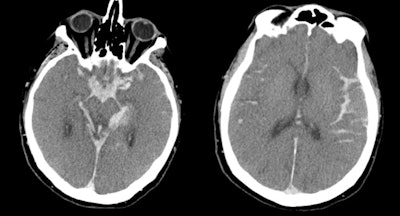

CT images show catastrophic subarachnoid hemorrhage. All images courtesy of Dr. Lenetta Boyce.

CT images show catastrophic subarachnoid hemorrhage. All images courtesy of Dr. Lenetta Boyce.Kralt is an independent consultant neuroradiologist specializing in forensic radiology and anthropology. He is co-author of the book "Post Mortem CT for Non-Suspicious Adult Deaths: An Introduction." Boyce is a consultant radiologist at Liverpool University Hospitals NHS Foundation Trust, specializing in musculoskeletal radiology and trauma, including stroke.

Boyce: You get used to the patterns of decomposition gas, so seeing portal venous gas is obviously normal in a person that's passed away and sometimes people that haven't been found for a long time have got extensive decomposition; there's a lot of surgical emphysema everywhere. You put the findings that you see up there in the perspective of the clinical situations. For example, a deceased person loses oxygenation of the brain, so the pseudosubarachnoid sign in the brain is a normal postmortem finding. I think the complexity of postmortem imaging is learning what's normal for the deceased.